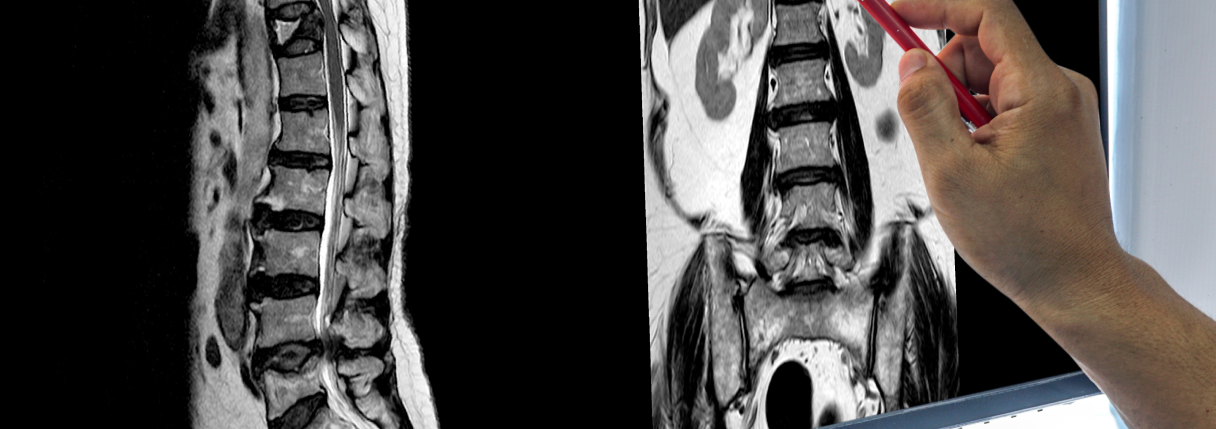

A tomografia da coluna, também chamada de tomografia computadorizada da coluna ou TC da coluna, é um exame de imagem que utiliza radiação ionizante para gerar imagens detalhadas em cortes transversais da coluna vertebral.

O exame permite avaliar com alta precisão as estruturas ósseas da coluna, incluindo vértebras, articulações, alinhamento vertebral e canais ósseos. Diferentemente da radiografia simples, a tomografia fornece uma visualização tridimensional, o que facilita a identificação de alterações estruturais que podem passar despercebidas em exames convencionais.

Em termos práticos, a tomografia da coluna mostra a anatomia óssea com clareza e profundidade, sendo fundamental em quadros mais complexos.